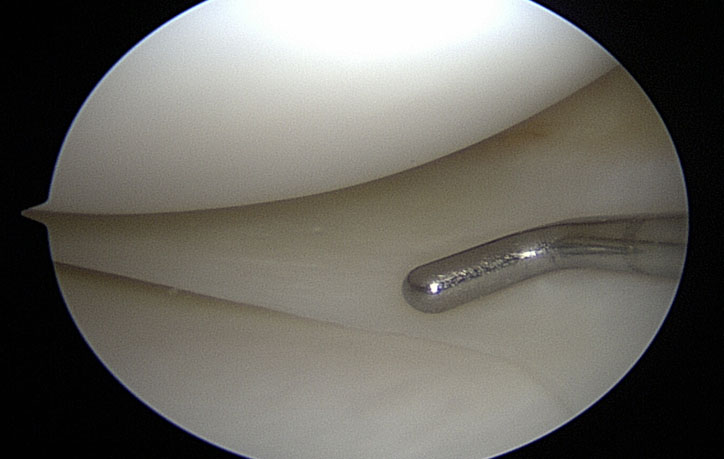

Reparación y remodelación de lesiones meniscales

Un menisco sano actúa como un amortiguador y un estabilizador a la vez que provee una superficie lisa para que la rodilla pueda deslizarse libremente. Una lesión meniscal altera este desplazamiento causando dolor y bloqueo, por lo que es fundamental realizar su reparación.